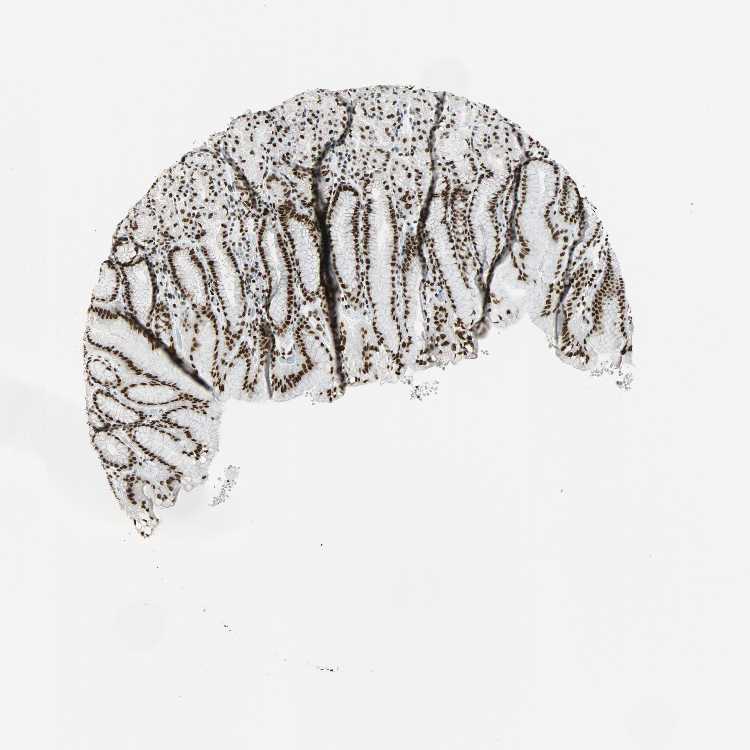

TISSUE PRIMARY DATA STOMACH Show tissue menu

STOMACH 1 - Antibody stainingi

Antibody staining in the annotated cell types in the current human tissue is reported as not detected, low, medium, or high, based on conventional immunohistochemistry profiling in selected tissues. This score is based on the combination of the staining intensity and fraction of stained cells.

Each image is clickable and will lead to virtual microscopy that enables deeper exploration of all samples and also displays staining intensity scores, fraction scores and subcellular localization as well as patient and tissue information for each sample.

Antibody HPA046440Antibody CAB004652

Glandular cells MediumHigh

STOMACH 2 - Antibody stainingi